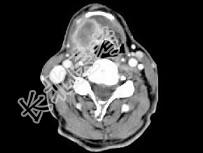

- 单项选择题男,63岁, 咽喉部不适约1年,近两个月经常咳嗽, 痰中带有血丝,CT如图所示, 最可能的诊断是 ( )

A、梨状窝癌

B、声门型喉癌

C、声门下型喉癌

D、声门上型喉癌

E、混合型喉癌